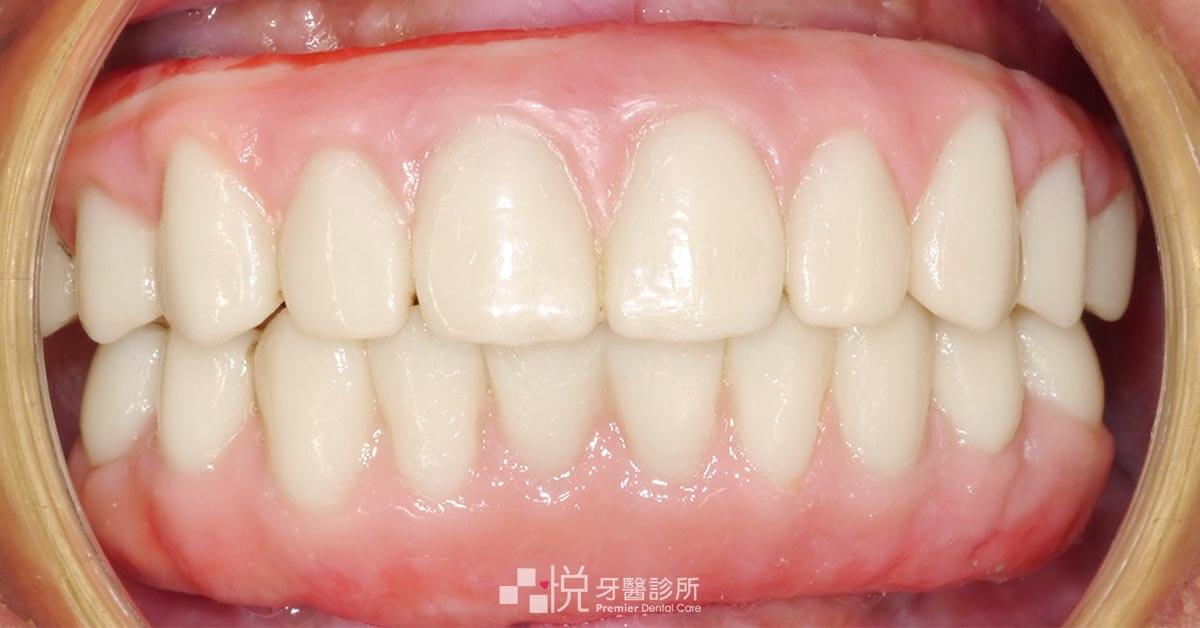

All-on-4 植牙手術復原後,陳媽媽原本看診時的表情僵硬也變成了開心的微笑,適應新假牙的生活,整個人都年輕了起來。

身為牙周醫師,能運用 All-on-4 手術的特性,幫助骨質不足的患者,用較短的重建期重拾一口好牙,是工作中讓我覺得很滿足的一件事。